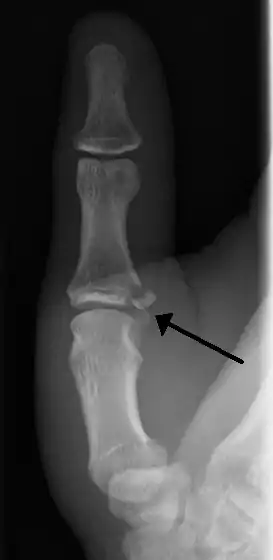

| Avulsion fractures of the ulnar base of the proximal phalanx of the thumb ( Gamekeeper's fracture ) | |

- Avulsion of distal UCL causing the pulling off of a bone chip off the proximal phalanx base.[7]

When approaching this type of injury, the physician must first determine whether there is an incomplete rupture (or sprain) of the UCL, or a complete rupture. If the UCL is completely disrupted, the physician must then determine whether there is interposition of the adductor aponeurosis (Stener lesion), or simply a complete rupture of the UCL with anatomic or near-anatomic position. Radiographs are helpful in determining the possible presence of an avulsion fracture of the proximal phalanx insertion site of the ulnar collateral ligament. Stress examination, or one done under fluoroscopic guidance, can help determine the integrity of the ligament.